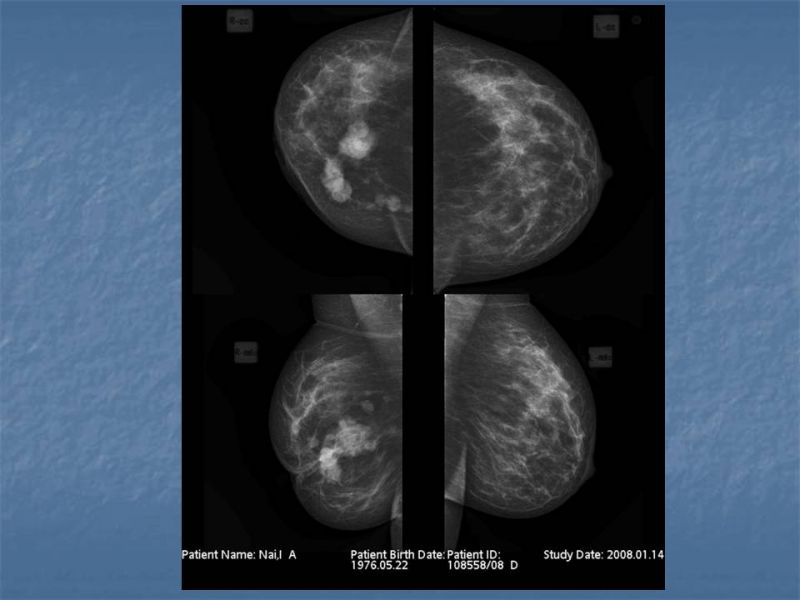

При отсутствии жалоб проходить УЗИ необходимо пациенткам возрастом 25–39 лет один раз в два года, старше 40 — ежегодно. УЗИ молочных желез после 40 лет важно проводить регулярно с целью профилактики онкологических заболеваний. Гормональные изменения, связанные с возрастными процессами, повышают риск появления новообразований.

Кому противопоказано

УЗИ практически не имеет противопоказаний. Однако важно отметить, что информативность обследования груди таким способом у женщин молодого возраста выше, поскольку ткани молочных желез с возрастом становятся более рыхлыми. Поэтому после 40 лет УЗИ в большинстве случаев сочетается с рентген-диагностикой (маммографией).